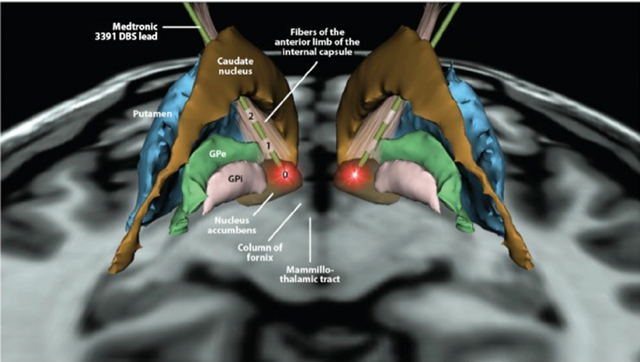

Según un artículo publicado en la revista Nature Communications, una parte del cerebro que está asociada con la motivación y el placer -el núcleo accumbens- también puede producir sueño.

La misma región del «sentirse bien» del cerebro que entra en acción para ayudarnos a disfrutar de la comida y el sexo también está involucrada en ponernos a dormir.

Científicos de la Universidad de Tsukuba en Japón han hallado que esta parte del cerebro está densamente poblada por receptores para una molécula que hace que nos durmamos cuando estamos aburridos.

Los investigadores japoneses han descubierto que el núcleo accumbens en el cerebro anterior tiene una capacidad extremadamente fuerte para inducir el sueño.

El núcleo accumbens desempeña un papel clave en el sistema de recompensas del cerebro, que libera dopamina y nos hace sentir placer cuando hacemos cosas que son productivas para nuestra supervivencia, como comer, hidratarse, practicar sexo o incluso socializar.

Pero en ausencia de estos estímulos motivacionales, la misma parte del cerebro hace que nos sintamos muy cansados.

El núcleo accumbens tiene muchos receptores que responden a un neurotransmisor, llamado adenosina, que ayuda a regular nuestro ciclo de sueño y de vigilia.

El autor principal Yo Oishi, de la Universidad de Tsukuba, ha comentado: «El clásico somnógeno adenosina es un fuerte candidato para evocar el efecto del sueño en el núcleo accumbens».

Los científicos han demostrado este fenómeno usando medicamentos y luz para estimular las células cerebrales en el núcleo accumbens de los ratones, que, encontraron, causaron que los ratones se durmieran.

Este descubrimiento podría ayudar para realizar tratamientos más seguros para el insomnio, así, ahora que sabemos más sobre el funcionamiento de la ubicación de estos receptores en el núcleo accumbens.

Los resultados pueden abrir nuevas vías terapéuticas para el tratamiento del insomnio y otros trastornos del sueño.

Los compuestos que activan los receptores A2A en el núcleo accumbens pueden abrir vías terapéuticas seguras para tratar el insomnio, que es uno de los problemas más comunes del sueño con una prevalencia estimada del 10-15 por ciento en la población general y del 30-60 por ciento en la población de ancianos.